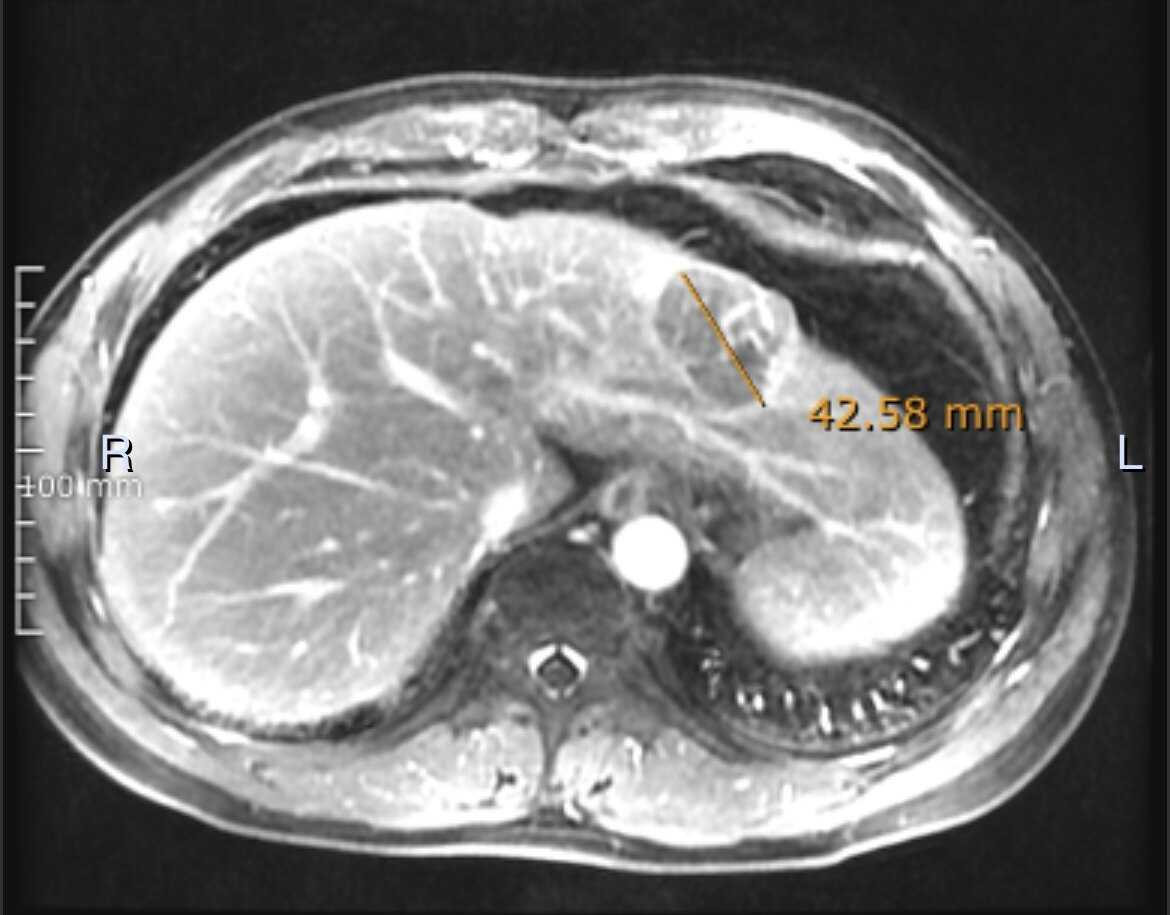

手术切除是早期肝癌安全(手术死亡率为0)、有效(5年生存率达到70%)、高性价比(报销前费用在3万元左右)的治疗方式。以下4例有乙肝病史,经定期筛查(肝脏B超和甲胎蛋白)发现的早期肝癌,手术切除后平均住院时间6天,无任何并发症,自费仅数千元。